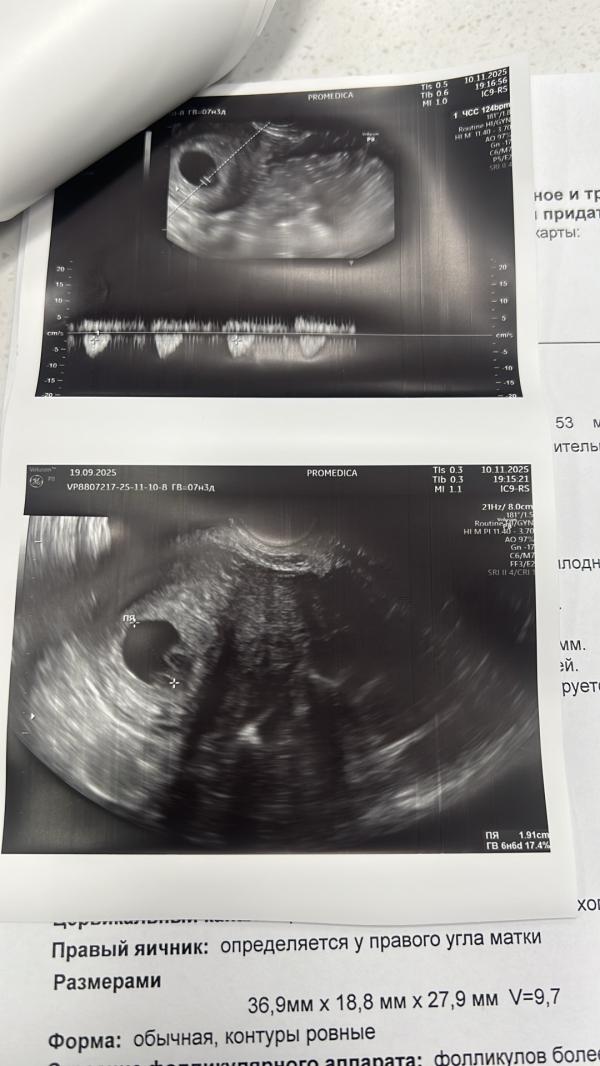

Я схожу с ума, у меня уже неделю не прекращается коричневая мазня, прям эндометрий. Я хожу на узи каждые 3 дня. Но не могут найти не гематому ни отслойку, прикрепление практически у дна матки, то есть высоко. Узи ты разводят руками, гинеколог сказала угрозы нет, тонуса нет, взяла мазки . Ничего тяжелого не поднимаю, с малышом все хорошо, но блин это же не норма. С первой беременностью не было такого. В четверг к врачу за результатами мазков и постановку на учет. Принимаю аспирин, думаю убрать его. Ничего не тянет, не болит, токса нет, грудь болит.

@annad_plan, ну вот на первом узи тоже говорили неделю назад, что пя прорастает и соединяется с кровотоком матери и повреждает эндометрий